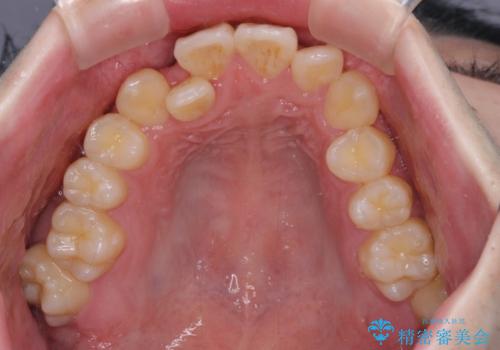

前歯のクロスバイトや八重歯の他に、左右最後臼歯のシザーズバイト(鋏状咬合)が認められました。

シザーズバイト改善のために補助装置を使用しながら、ワイヤー装置にて全体の歯列を整えることとしました。

シザーズバイトは強く咬合する奥歯を移動させるため、多くの場合においてワイヤー矯正の装置のみでは改善が困難となります。

奥歯の咬み合わせ改善は治療初期からしっかりとアプローチする必要があるため、補助装置を積極的に利用します。